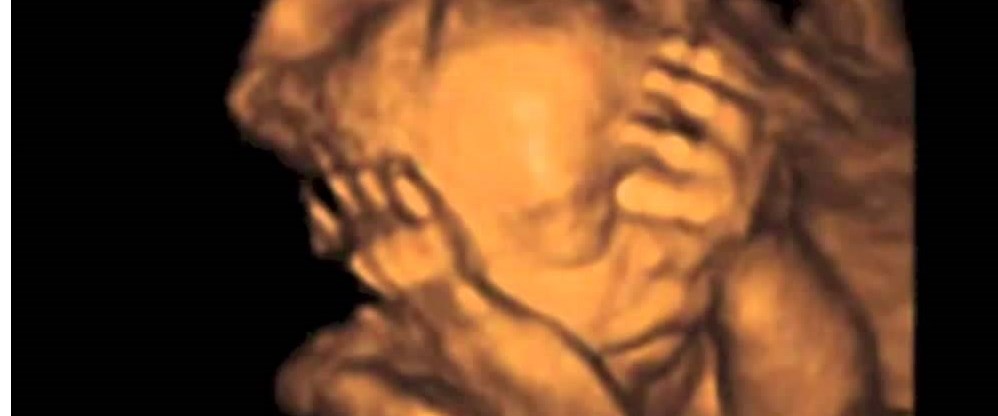

hamilelikte bebeğin toplanması

hamilelikte bebeğin toplanması.